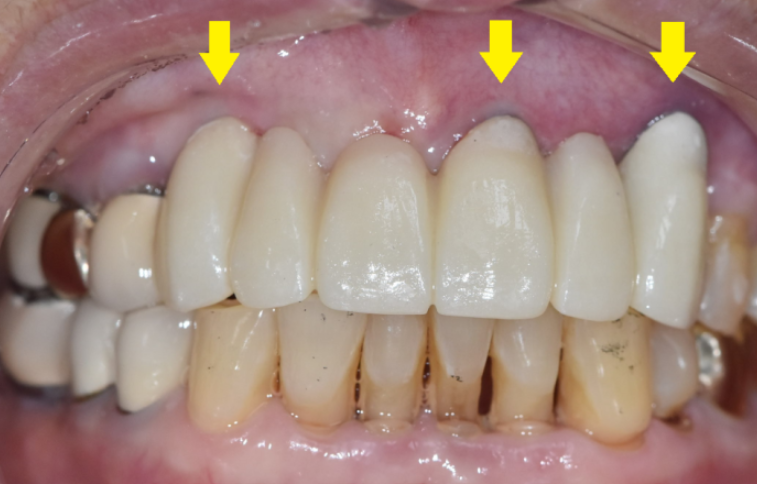

4월에 수술을 하고 3개월정도 지나

머리를 만들어 드렸는데요.

똑같이 6개를 묶은 앞니 브릿지 형태인데

임플란트는 3개를 심어 6개로 만들어 드렸습니다.